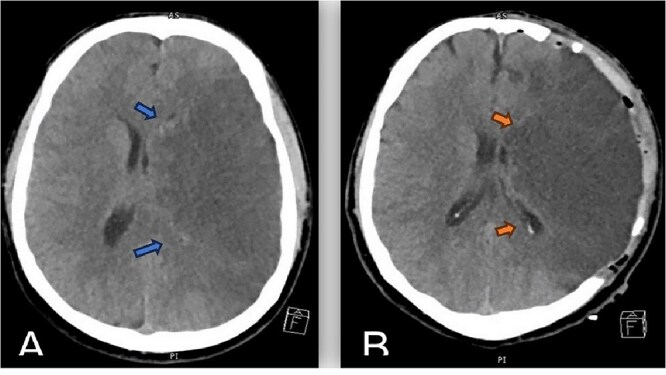

Malignant Middle cerebral artery (MCA) infarction is characterized by rapid neurological deterioration due to cerebral edema. Spasticity, a common sequela of stroke, typically occurs days to weeks after the initial event. However, an acute onset of spasticity at presentation is extremely rare. We report a case of a 40-year-old male patient who presented with spasticity accompanied by aphasia and decreased consciousness. Left MCA occlusion was demonstrated on Computed tomography (CT) angiography. Cerebral edema developed rapidly, requiring decompressive hemicraniectomy (DH). The patient was a known smoker with androgenic anabolic steroid use. This case represents a rare presentation of malignant MCA infarction with acute spasticity and adds a unique aspect to the clinical spectrum of stroke presentation. This case emphasizes the need for awareness of atypical stroke presentation and the potential role of anabolic steroids in stroke risk.